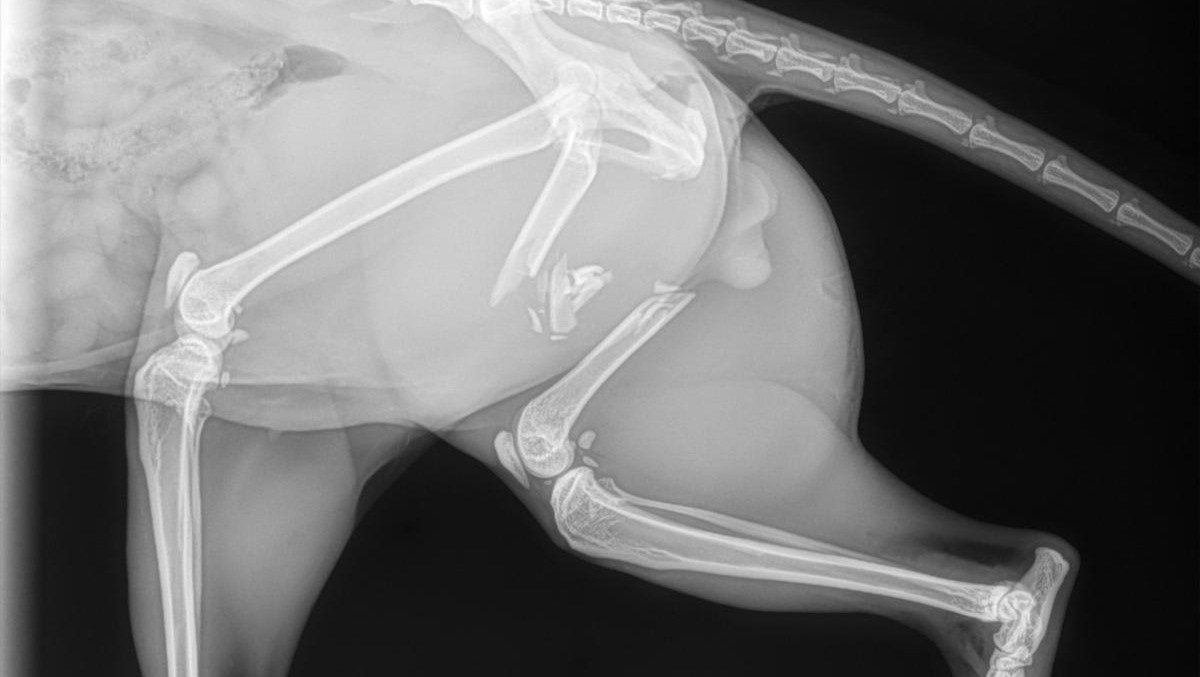

Hi, my name is Caelan, and I need urgent help funding my cats leg surgery. Tragically, he was hit by a car on October 22nd, left alone by the driver, until I found him later hiding and afraid in the back of a shed. Poor baby Taz had fractured his back left femur, leaving tons of bone fragments floating in his leg and in immense amounts of pain. As any good cat parent would, I rushed him to the ER immediately, and received the hard news that his leg was broken, and he's in Dire need of surgery. The surgery is set for Halloween, and as a young adult living in Vancouver, I need all the help and support I can receive in order to keep my best friend happy and healthy. Taz is a very active and energetic cat who wouldn't be able to live life the way he wants with only three legs. Help a desperate cat dad in need, any donations or sharing the page would help greatly!